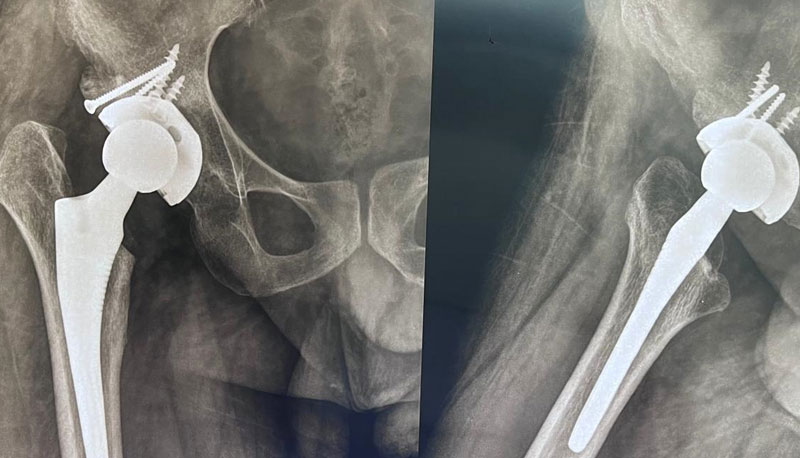

A 32-year-old male with a 7-year history of hip osteoarthritis underwent total hip replacement in 2018, with reconstruction of a false acetabulum using bone graft and screws. A recent X-ray shows a well-fixed implant in good alignment, and the patient reports pain-free walking with a good range of motion.